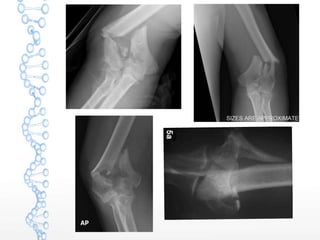

Associated injuries

 Coronoid fractures

 Radial head fratures

 Nerve injury

 Vascular injury

TERRIBLE TRIAD